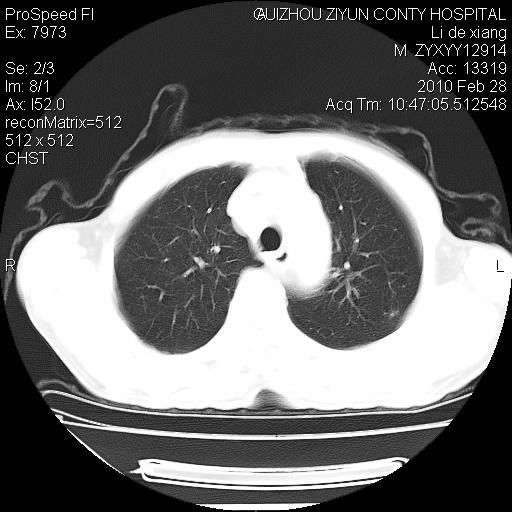

标题: CT24776:男 71Y 咳嗽咳痰胸痛两月,伴声音嘶哑。 [打印本页]

标题: CT24776:男 71Y 咳嗽咳痰胸痛两月,伴声音嘶哑。

左侧中央型肺癌伴左肺上叶阻塞性肺炎及节段性不张可能性大,建议纤支镜检查!

左侧中央型肺癌伴左肺上叶阻塞性肺炎及节段性不张可能性大,建议纤支镜检查!纵隔淋巴结转移.

左肺门部肿块,伴左上肺斑块影,周边模糊,支持左肺中央型肺癌伴节段性不张及阻塞性肺炎,结合支气管镜检查。

左上叶支气管狭窄,阻塞性病变,肺门肿块,纵隔及肺门淋巴结增大,中央性肺癌